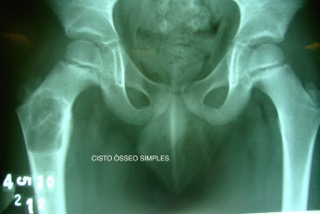

Cisto ósseo simples

O cisto ósseo simples é uma lesao benigna ativa preenchida com liquido sanguinolento. Em nossos procedimentos tratamos conservadoramente quando pequenos e em membros superiores, porem cirúrgicamente quando em membros inferiores, com altos indices de bons resultados.